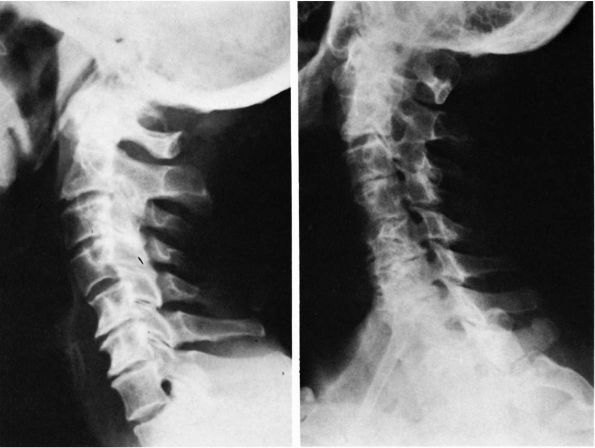

subluxation or C1-C2 rotatory displacement (rotatory subluxation of

childhood; Figure 11-2).

FIGURE 11-2.

Rotatory subluxation, C1 on C2. This open mouth view is consistent with atlantoaxial rotatory subluxation. There is tilt of the skull as well as a shift of the lateral masses of C1 on C2, with overlap of the lateral mass of C1 on C2 on the left side. Cineradiography or dynamic CT scan is the best method to confirm fixed rotatory subluxation of C1 on C2. |